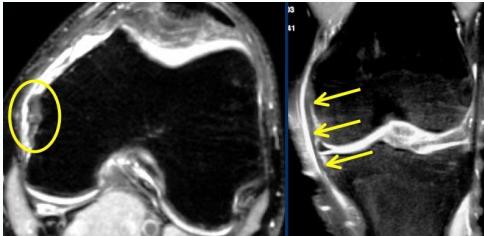

MRI

- Best for assessing soft tissue damage